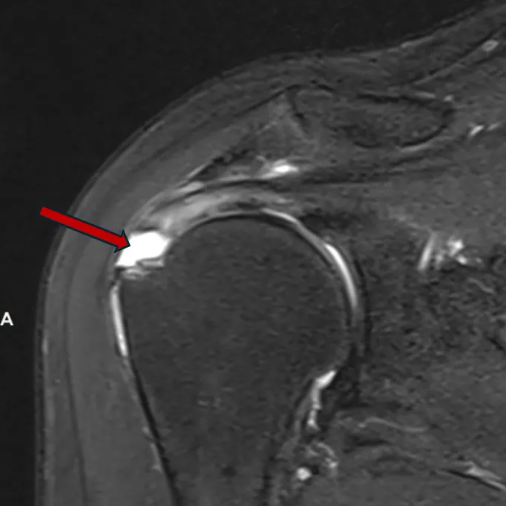

肩袖损伤在MRI图像上的表现

肩袖由冈上肌、冈下肌、肩胛下肌和小圆肌的肌腱共同构成,形似袖套包裹肱骨头。正常情况下,肌腱在MRI图像上呈现为均匀的低信号(黑色)。当发生损伤时,可能表现为肌腱增粗、连续性中断、信号异常,在压脂序列上信号增高(白色)。

图1-2.正常肌腱表现为黑色(橙色箭头所示)

冈上肌肌腱滑囊侧部分撕裂,伴滑囊、关节囊积液(紫色箭头所示)

冈上肌腱完全撕裂,肌腱挛缩(白色,深红色箭头所示)